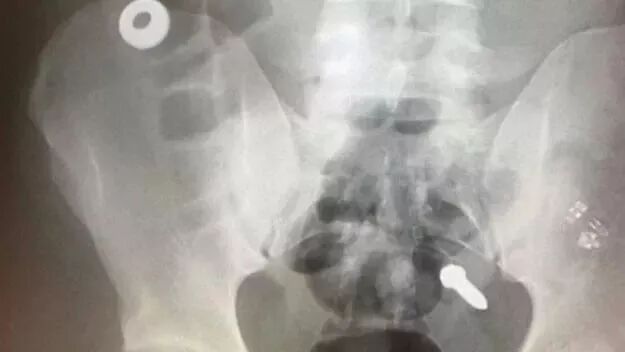

所謂的“狂吃”不是胃口大,而是看見什麼吃什麼,包括灰塵、掉落的

鐵釘、螺絲帽、垃圾桶鐵皮等不正常的東西,全都進了他的肚子。

正是因為他什麼都敢吃,導致他的胃功能經常受到損害,光是專門送他去

醫院檢查治療都有20多次,在他身上花費了近100多萬美元......

一時間,狂吃哥的“光榮事蹟”在監獄里傳開了,其他獄友看到這哥們

受到如此“優待”之後,紛紛表示不服,也開始狠下心來吃螺絲吞鐵釘!

於是就有了以下搞笑的畫面:犯人們對伙食不滿意了,吃鐵釘!住得不滿

意了,吃鐵釘!總之,只要有什麼不滿意的,吃鐵釘就完了!